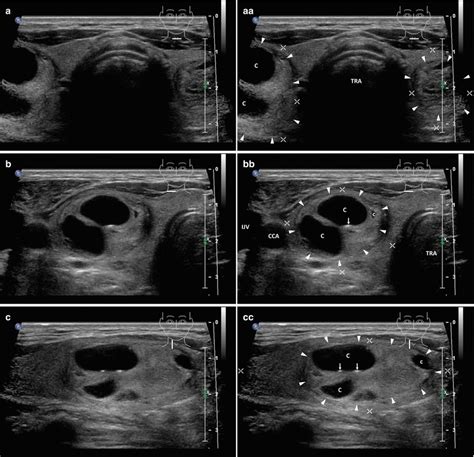

Ultrasound remains the cornerstone imaging technique, offering high-resolution visualization of thyroid architecture. In multinodular goiters, ultrasound reveals multiple discrete hypoechoic or isoechoic nodules of varying sizes, often with calcifications or cystic changes. A solitary adenoma typically appears as a well-defined hypo- or iso-echoic nodule with characteristic peripheral (termed “capsule”) or internal vascularity on Doppler studies.

| Ultrasound Features | Multinodular goiters display multifocal nodules with variable echogenicity; adenomas are solitary, well-circumscribed, and often demonstrate a "halo sign" indicating capsule. |